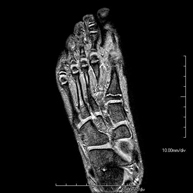

- Foot MRI

Examination for the study of injuries to tendons, muscles and small joints. Allows for effective assessment of cartilage injuries. It is also very useful for completing the preliminary ultrasound examination. It is a radiation-free procedure. It lasts approximately 20 minutes.